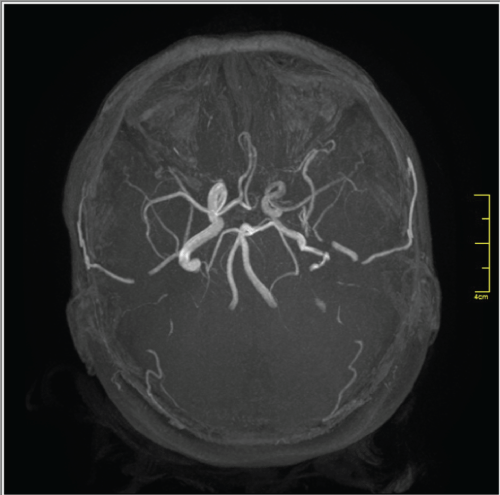

A 50-year-old woman presented with a four-year history of left-sided pulsatile tinnitus and hearing impairment. Otoscopy revealed a reddish mass behind the inferior half of the left tympanic membrane. Audiometric evaluation showed mild conductive hearing loss in the left ear. High-resolution CT scanning of the temporal bone was performed. On the CT scan of the temporal bone, a left-sided aberrant ICA entering the middle ear cavity through an enlarged inferior tympanic canaliculus was observed (Figure 1). The right temporal bone was normal. MRA showed a reduced diameter and lateralization of the left ICA (Figure 2A and Figure 2B). The vertical segment of the ICA was lateral and posterior to a line drawn vertically through the vestibule. Hypoplasia of the A1 segment of left ACA was also identified.

Figure 2a: Magnetic resonance angiography showing reduced diameter and lateralization of the left internal carotid artery (ICA). The right ICA is normal. Hypoplasia of the A1 segment of the left anterior cerebral artery (ACA) is also noted.

Figure 2b: Magnetic resonance angiography showing reduced diameter and lateralization of the left internal carotid artery (ICA). The right ICA is normal. Hypoplasia of the A1 segment of the left anterior cerebral artery (ACA) is also noted.

The misdiagnosis of aberrant ICA can result in fatal bleeding or other life-threatening complications. Suspicion of a retro-tympanic mass in the middle ear necessitates radiographic investigation. CT scan of the temporal bone is considered as one of the most reliable methods to diagnose an aberrant ICA. On CT scan, aberrant ICA is recognized by; an enhanced mass in the hypotympanum, a deficient bony plate along the tympanic portion of the ICA, absence of the vertical segment of the carotid canal, and a reduced diameter of ICA that runs adjacent to the jugular bulb [2-5]. MRA can be used as an additional tool for the definitive diagnosis and it also provides excellent visualization of the intracranial and extracranial circulation. The important features at angiography are; a reduced diameter of the tympanic ICA, the vertical segment of the ICA is lateral to a line drawn vertically through the vestibule [2,5]. In our case, CT and MRA showed all the characteristic features of aberrant ICA. In addition, hypoplasia of the A1 segment of the anterior cerebral artery was identified on MRA. In a review of the literature, we noted various other reports of an aberrant ICA in which hypoplasia of the A1 segment of the ACA was noted as an incidental finding [8-11]. Hypoplasia of the A1 segment of the ACA is reported to be present in 10% of autopsies [12]. The relationship between ipsilateral absence or hypoplasia of the A1 segment and a reduced caliber of the ICA has been further reported by Kane et al. [13] in a study of intracranial MR angiograms.